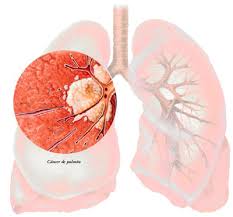

CANCER DEL PULMON

El cáncer de pulmón es uno de los cánceres más comunes en el mundo. Es la principal causa de muerte por cáncer entre los hombres y las mujeres en los Estados Unidos. El fumar cigarrillos causa la mayoría de los cánceres de pulmón. A mayor cantidad de cigarrillos diarios que fume al día y cuanto más joven se comienza a fumar, mayor será el riesgo de desarrollar un cáncer de pulmón. La exposición a altos niveles de contaminación, radiación y asbesto también puede aumentar el riesgo.

Los síntomas comunes del cáncer de pulmón incluyen:

- Una tos que no desaparece y empeora con el tiempo

- Dolor constante en el pecho

- Tos con expectoración con sangre

- Falta de aire, silbidos al respirar o ronquera

- Problemas repetidos por neumonía o bronquitis

- Inflamación del cuello y la cara

- Pérdida del apetito o pérdida de peso

- Fatiga

Existen muchos tipos de cáncer de pulmón. Cada uno de ellos crece y se disemina de un modo distinto y se trata de una forma diferente. El tratamiento también depende del estadio o de qué tan avanzado se encuentre. El tratamiento puede incluir quimioterapia, radiación y cirugía.